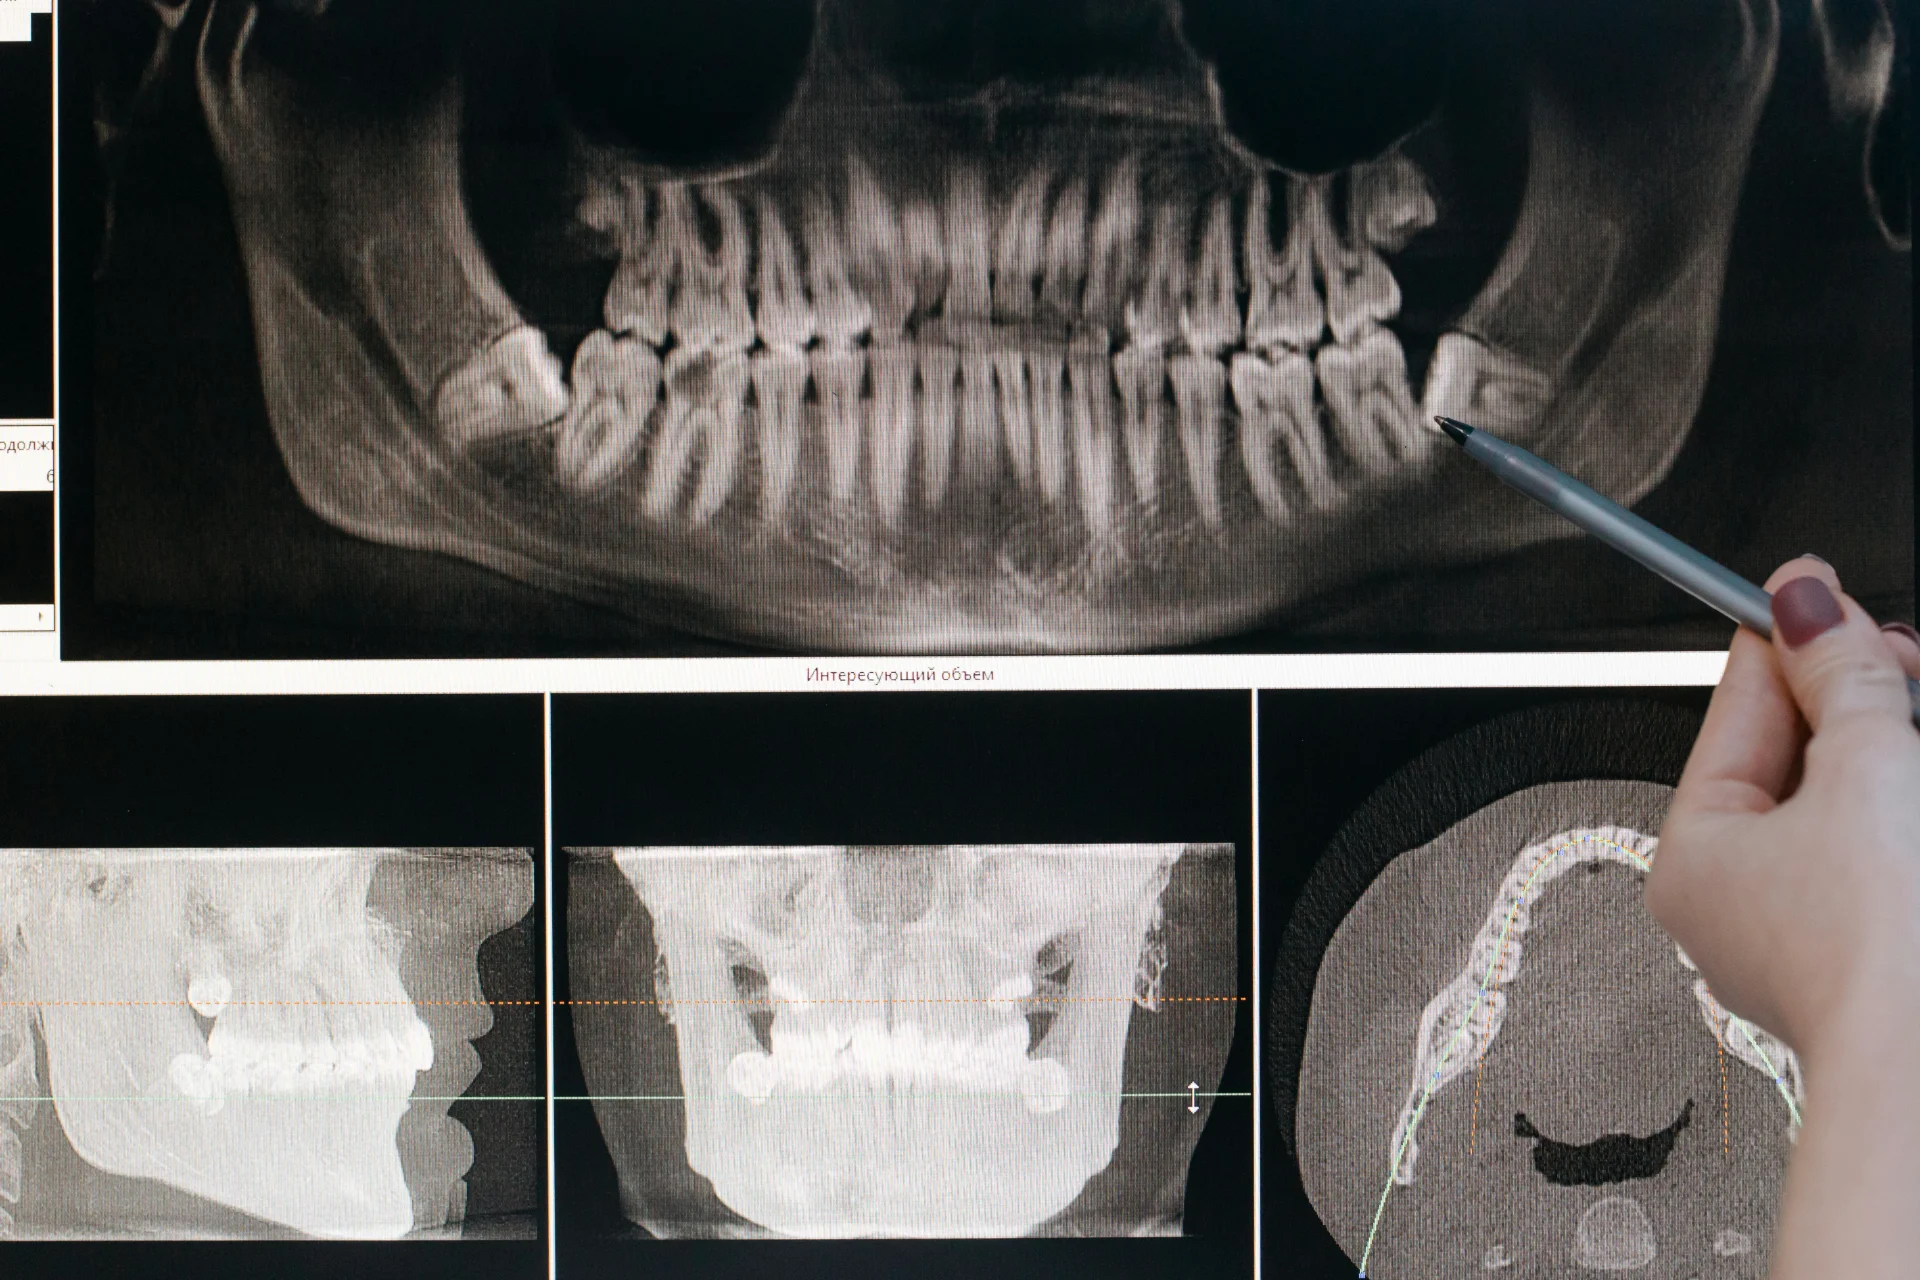

Panoramic digital X-rays provide a comprehensive view of all teeth, jaws, sinuses, and surrounding structures in a single image. These extraoral radiographs serve multiple purposes, including screening for impacted teeth, evaluating jaw development, detecting cysts or tumors, and planning complex treatments such as implant placement or orthodontics. Modern panoramic units often include additional imaging modes such as cephalometric views for orthodontic analysis and TMJ-specific projections.

Cone beam computed tomography represents a major advancement in three-dimensional dental imaging, providing detailed volumetric data that two-dimensional radiographs cannot capture. CBCT scanners rotate around the patient's head, capturing hundreds of images from different angles that computer software assembles into a 3D model of dental and facial structures. This technology has become increasingly important for complex diagnostic scenarios and treatment planning.

Implant dentistry has particularly benefited from CBCT imaging capabilities. The technology allows precise measurement of available bone height and width, identification of vital structures such as nerves and sinuses, assessment of bone density, and virtual placement of implants before surgery begins. This comprehensive planning reduces surgical complications, improves implant positioning for optimal function and aesthetics, and enables the fabrication of surgical guides that translate virtual plans to actual procedures with remarkable accuracy.

Endodontic applications of CBCT include detecting accessory canals that might harbor infection, identifying root fractures that can be difficult to see on conventional radiographs, evaluating periapical pathology in three dimensions, and assessing complex root anatomy before treatment. Research demonstrates that CBCT imaging can reveal details missed on two-dimensional films, particularly in cases involving extra canals or unusual root configurations.

Orthodontic treatment planning utilizes CBCT data to analyze airway dimensions, assess impacted teeth positions, evaluate jaw relationships in all three planes of space, and plan skeletal anchorage device placement. The ability to visualize the complete craniofacial complex helps orthodontists make more informed decisions about treatment approaches and predict outcomes more accurately. Some practices now use CBCT scans as part of comprehensive orthodontic records for complex cases.

While CBCT provides exceptional diagnostic information, appropriate use guidelines recommend limiting scans to situations where the three-dimensional data will meaningfully influence treatment decisions. The radiation dose from CBCT varies depending on the field of view and resolution settings, but typically exceeds that of conventional dental radiographs. Evidence-based selection criteria ensure that the benefits of CBCT imaging justify the radiation exposure for each individual patient.